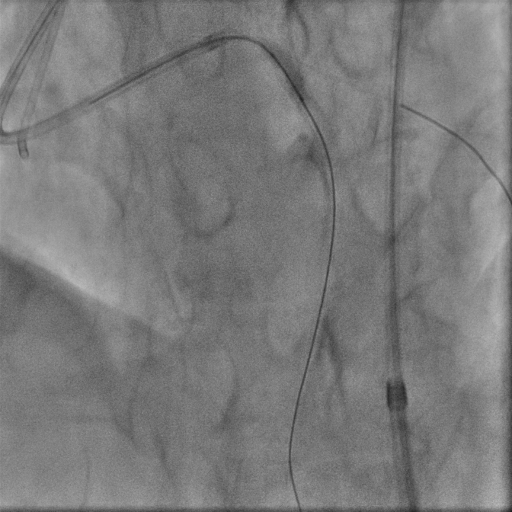

We used 7Fr EBU 3.5 guiding catheter to provide strong support, with diagnostic JR4 as contralateral injection. We started with antegrade wiring, which turned out to be difficult. There seemed to be a little bit of stump in the proximal cap but wire manipulation towards the stump was difficult, owing to the bending angle right at left main trifurcation as well as presence of calcium nodule in ostial stent. We failed proximal cap puncture despite escalating to Conquest Pro 12 loaded in single lumen microcatheter (SLC), which often backed off upon wire probing. Balloon assisted power puncture failed as well. To overcome the acute bending hindering wiring force exertion, we switched to an angulated microcatheter SuperCross120. By this manouvre we were able to advance our wire slightly into very proximal part of LAD stent, but it was deviated from central lumen and we failed to track down SLC. Hence we switched to parallel wire technique with use of a dual lumen microcatheter. The 2nd wire was able to reach the distal part of the stent only despite switching back to SLC and 1.0 balloon dilatation. Our next step was using the 0.9mm laser catheter to perform calcium modification within the ISR segment sequentially with saline, blood and contrast medium. After this manouvre, LAD was finally successfully wired with Fielder XTA, followed by balloon dilatation under IVUS guidance. Balloon expansion in ISR was suboptimal, hence it was treated with shockwave and drug coated balloon.